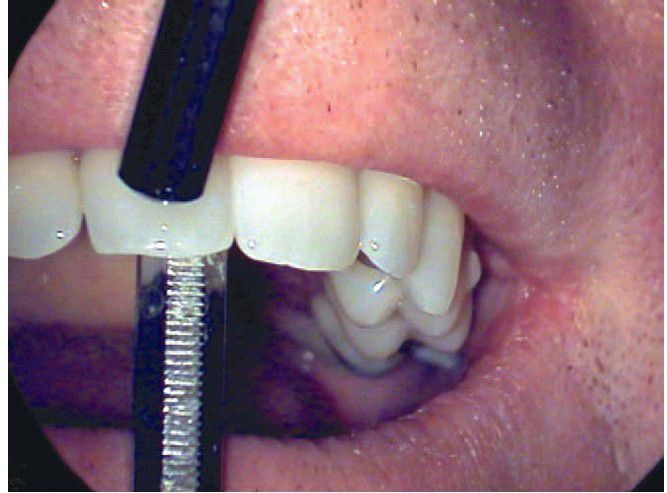

Mobility testing of a tooth, using the back ends of two mirror handles.